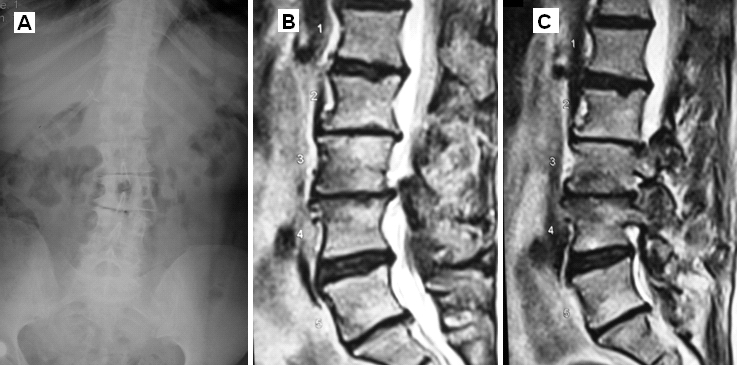

Lomber Skolyoz MRG Spinal Stenoz

Resim 2: MRG'de L4-L5 seviyesinde kanalın önden ve arkadan daraldığı (spinal stenoz) ve L3-L4 seviyesinde diskin belirgin yıprandığı görülmektedir.